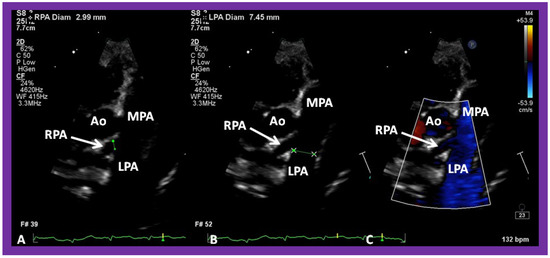

Figure 12. A selected video frame from a parasternal long axis view with color flow mapping of another patient with tricuspid atresia and transposition of the great arteries demonstrating the left atrium (LA), left ventricle (LV), a small right ventricle (RV) and a moderate sized ventricular septal defect (VSD). The vessel coming off the LV bifurcates into right (RPA) and left (LPA) pulmonary arteries. Reproduced from Reference [29]. PA, pulmonary artery.

The relationship of the great arteries is examined next in order to classify them into various types, as mentioned above. The relationship of the great arteries (Figure 2, top) is established by following the vessels arising from the ventricles until the pulmonary artery (PA) bifurcation or aortic arch. In Type I patients with normally related great arteries, the aorta arises from the LV (Figure 10) and in Type II patients with transposition of the great arteries, the PA arises from the LV (Figure 11; Figure 12). In Type II patients, the blood vessel arising from the LV should be traced to demonstrate its branching into the right and left PAs (Figure 11; Figure 12). In Type III patients, it may be a little more difficult to assign the great artery relationship and, sometimes, other imaging studies, including angiography, may be needed to define the great artery relationship. In Type IV with truncus arteriosus, the limited data suggest that this can be performed by echocardiography (Figure 13; Figure 15). In the example shown [31], the atretic tricuspid valve (Figure 13a and Figure 14a), VSD (Figure 13b and Figure 14b), hypoplastic RV (Figure 14a), single vessel (truncus) arising from the heart (Figure 13c,d, and Figure 14c,d), and origin of the PA and its division into branch PAs (Figure 13d, and Figure 14c,d) were demonstrated.

In Type II patients, the VSD may be small, causing obstruction to blood flow to the systemic circuit, and, therefore, the size of the VSD should be ascertained by 2D (Figure 11 and Figure 12), color Doppler (Figure 12), pulsed (Figure 15) and CW Doppler, as necessary. In these Type II patients, a high VSD velocity is indicative of subaortic obstruction. Interrogation of the LV outflow and PA region may reveal pulmonary or subpulmonary stenosis; the higher the velocity, the more severe is the obstruction. Studies from the suprasternal notch may show aortic coarctation (Figure 16), which is common in patients with Type II anatomy.